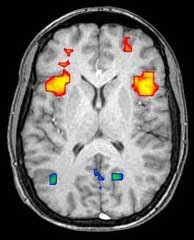

Here is a picture of a brain scan of a person whose brain is performing some function (exactly what function is irrelevant to what follows, but it could be, for example, speaking a language, receiving a reward in the brain, or planning a task). What does the scan show?

Figure 4. Source: https://en.wikipedia.org/wiki/Neuroimaging#/media/File:FMRIscan.jpg

When we look at the image of the brain scan, one might well think that there is activity only in the areas that are colored, and that they are therefore responsible for performing the given function.

At least that was my immediate thought when I first started looking at these kinds of pictures.

The problem is that it's just not correct, and it's actually quite unfortunate to look at it that way because it gives rise to two whole wrong ideas about how the brain works.

- On the one hand, one could get the idea that one only uses a small part of the brain, and

- partly it gives life to the idea that a specific center in the brain is solely responsible for a given function.

In the image above, there are two areas that are colored green. In these areas, the activity in the second measurement was actually less than in the baseline measurement. Does this mean that these areas have nothing to do with the given function? Or is it precisely the reduced activity in interaction with the increased activity elsewhere that makes the brain perform the given function? Translated into our football analogy, it could be a player who failed to run offside and thus created a prerequisite for the scoring player to score.